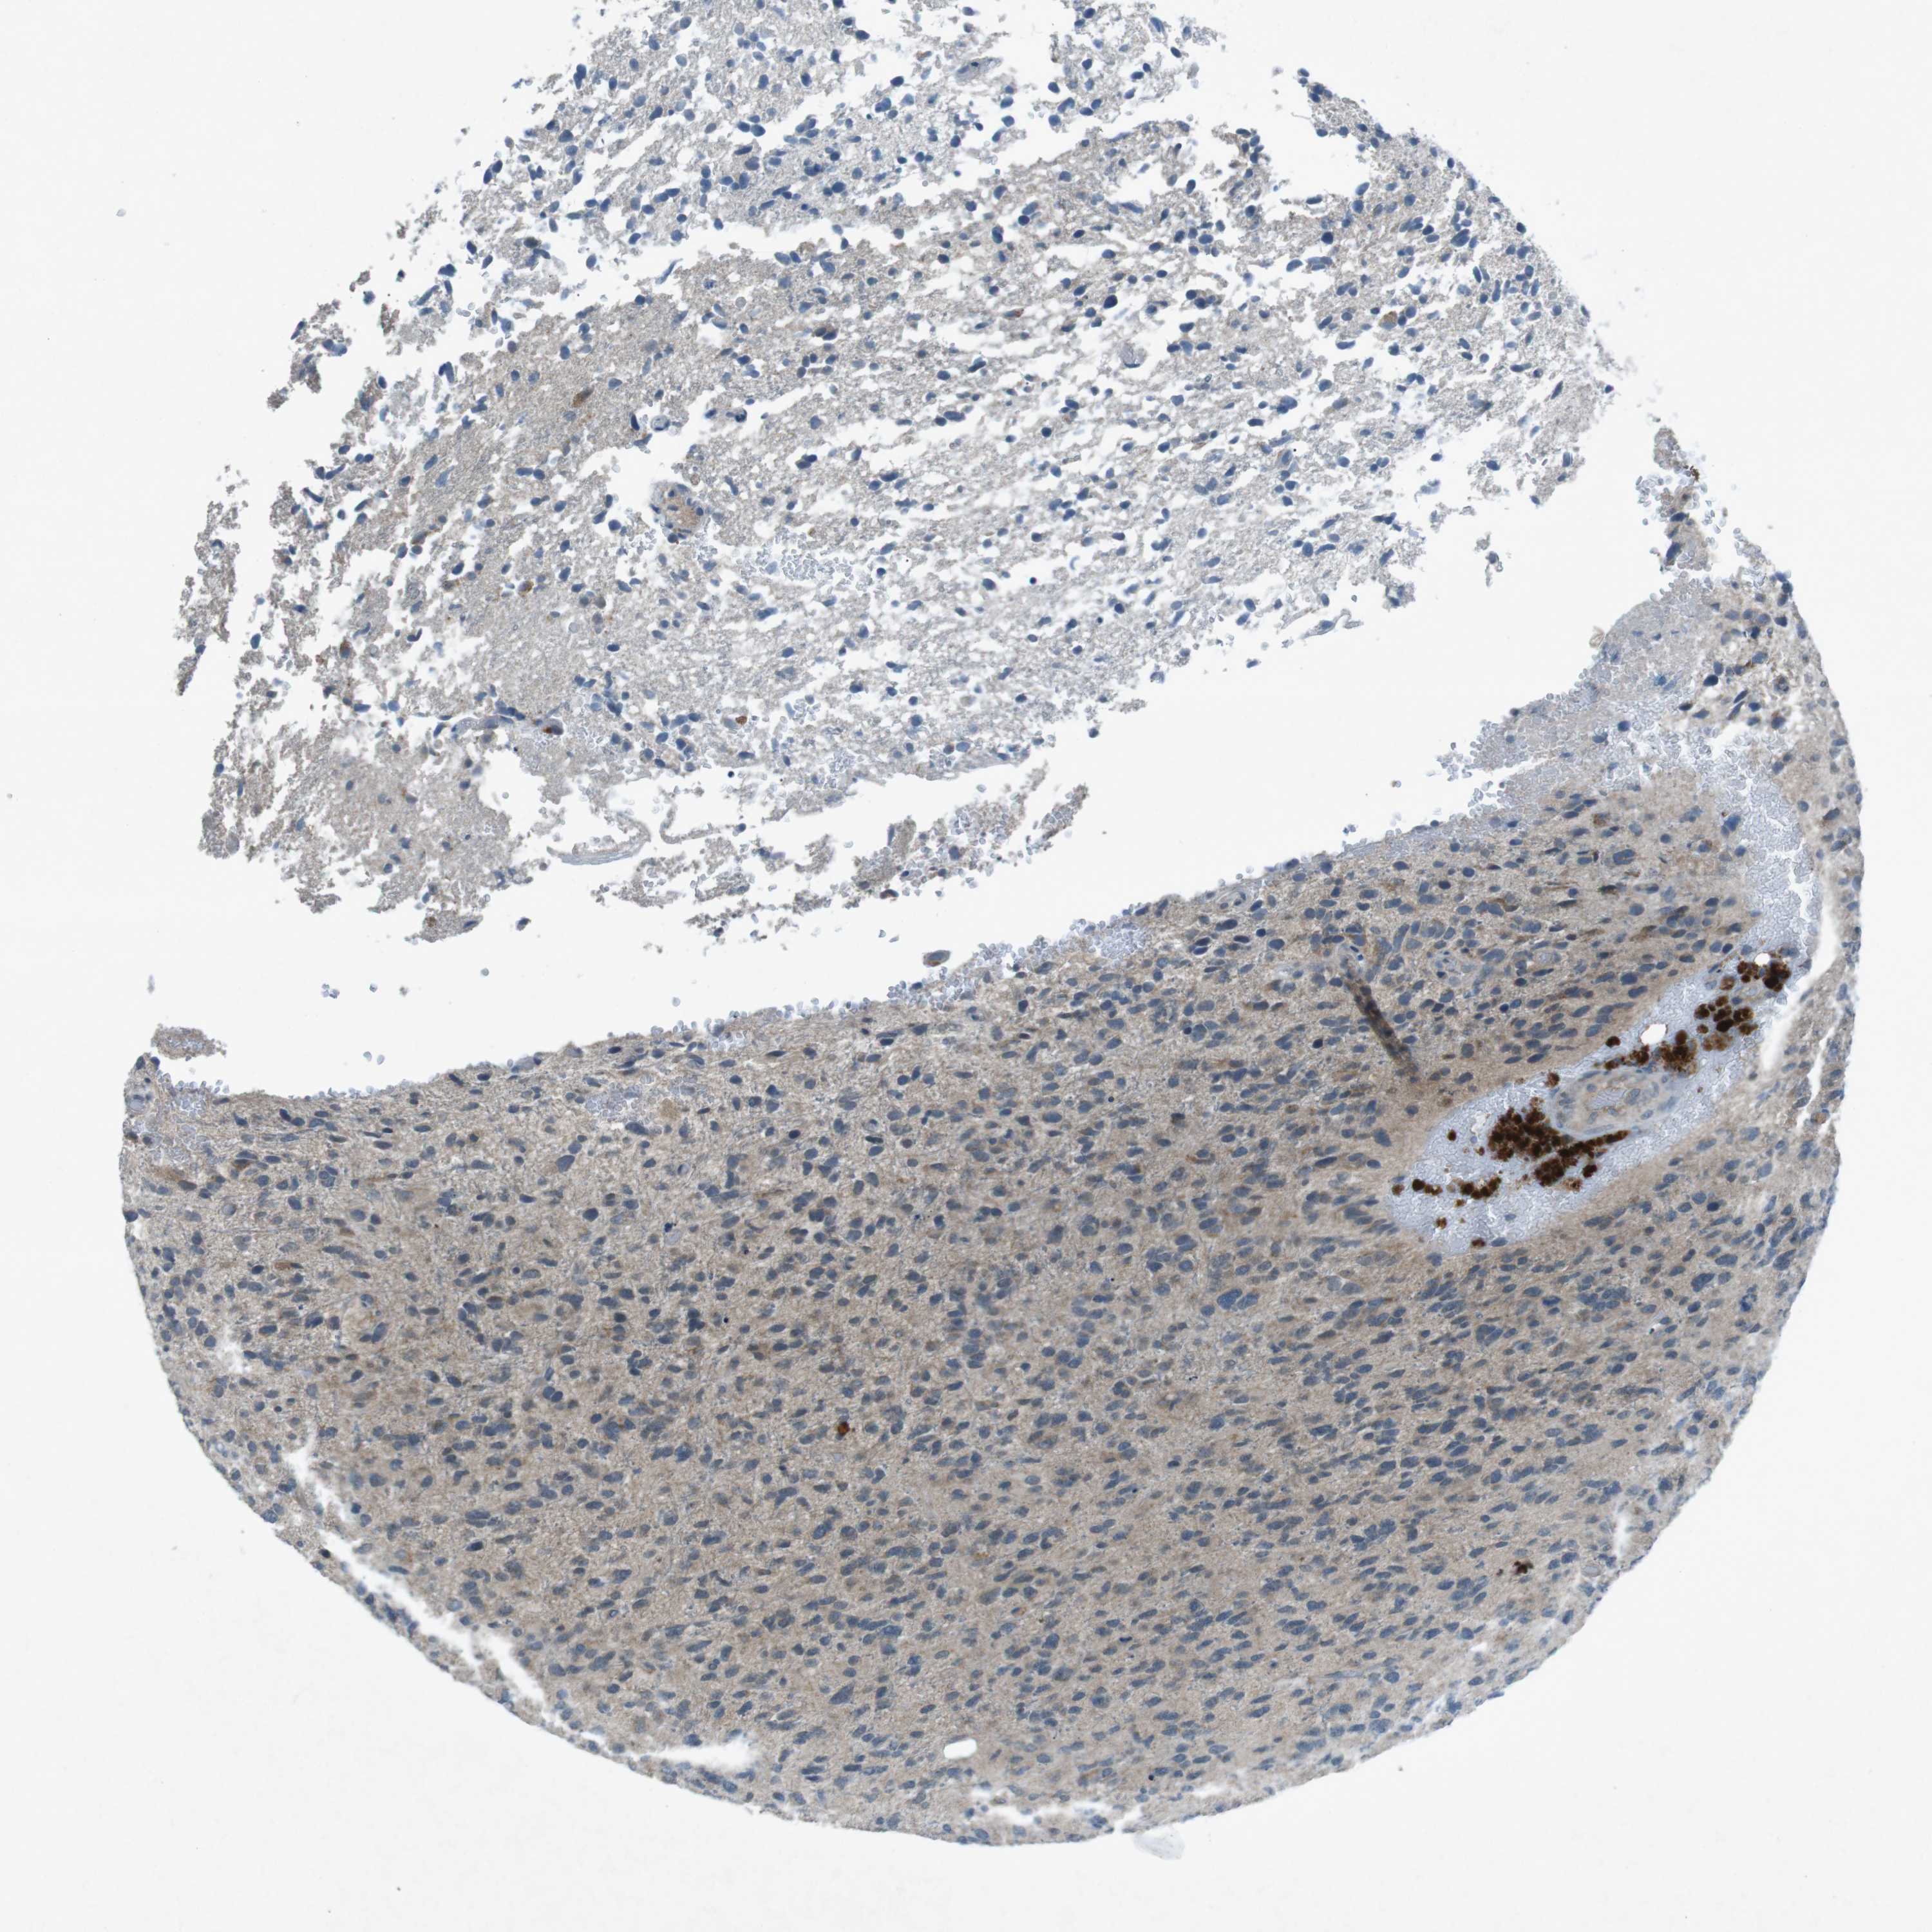

GLIOMA - Protein expressioni

A mouse-over function shows sample information and annotation data. Click on an image to view it in a full screen mode. Samples can be filtered based on level of antibody staining by selecting one or several of the following categories: high, medium, low and not detected. The assay and annotation is described here.

Note that samples used for immunohistochemistry by the Human Protein Atlas do not correspond to samples in the TCGA dataset.

Antibody stainingi

Antibody staining in the annotated cell types in the current human tissue is reported as not detected, low, medium, or high, based on conventional immunohistochemistry profiling in selected tissues. This score is based on the combination of the staining intensity and fraction of stained cells.

Each image is clickable and will lead to virtual microscopy that enables deeper exploration of all samples and also displays staining intensity scores, fraction scores and subcellular localization as well as patient and tissue information for each sample.

Antibody CAB016545

Staining

High

Medium

Low

Not detected

Intensity

Strong

Moderate

Weak

Negative

Quantity

>75%

75%-25%

<25%

None

Location

Nuclear

Cytoplasmic/membranous

Cytoplasmic/membranous,nuclear

Glioma, malignant, High grade

Glioma, malignant, Low grade